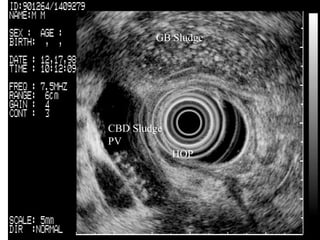

CBD Sludge  PV  HOP   GB Sludge

Gallbladder sludge and stone